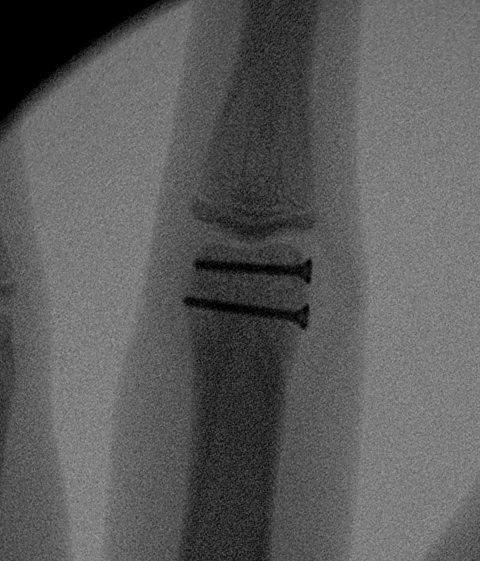

B. Long oblique / spiral fractures

Definition

- fracture must be at lease 2 x diameter bone

- can treat with 2 x lag screws

- one perpedicular to fracture to lag

- one perpendicular to shaft to resist shear

Options

- percutaneous K wires / screw fixation / plating